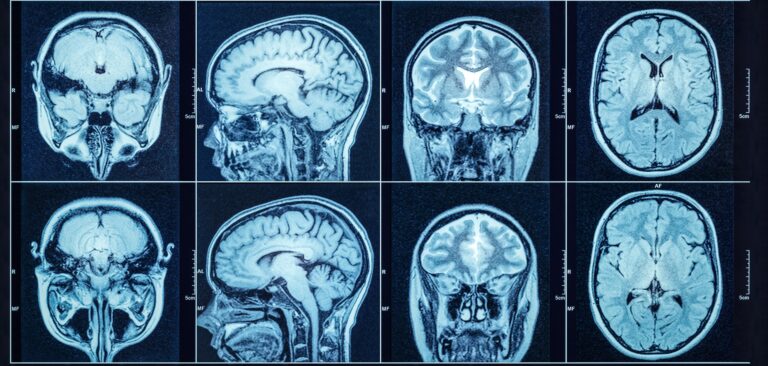

Persistent or severe headaches

Nausea or vomiting

Seizures or vision problems

Difficulty speaking or understanding speech

Personality or mood changes

Because the brain controls so many vital functions, even small tumors can have serious effects. Some brain tumors are benign (non-cancerous), while others are malignant and may grow rapidly. In either case, early diagnosis leads to more treatment options and better outcomes.

During Brain Cancer Awareness Month, we’re committed to spreading knowledge, offering support, and encouraging regular check-ups when symptoms appear.